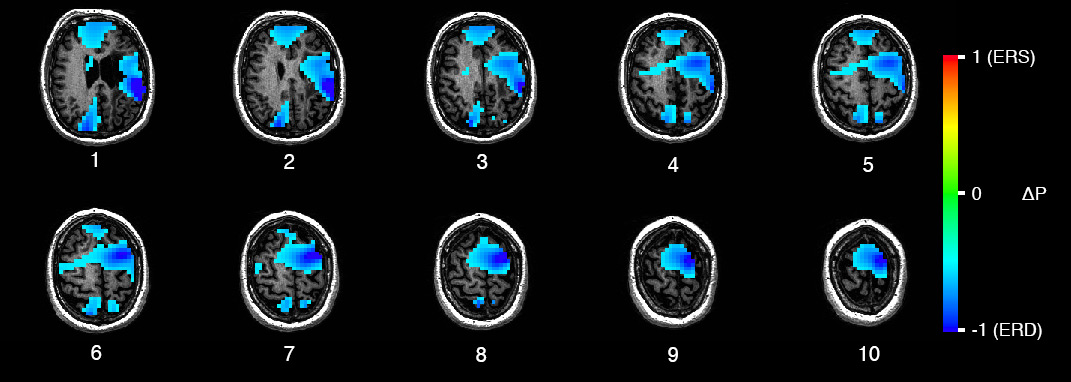

Patient Validation of a Motor Imagery-based Neurofeedback Paradigm (2017)

Undergraduate Honours Project for my B.Sc. in Neuroscience at Dalhousie.

Designed and implemented digital signal processing and analysis pipelines for MEG data to evaluate a motor imagery–based neurofeedback paradigm in stroke patients. Developed preprocessing, artifact rejection, and source localization workflows in Python, supporting further clinical work in patients with stroke-related upper limb dysfunction.